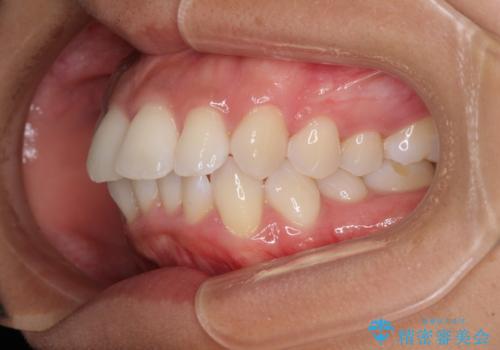

- 下唇が突き出るような口元の突出感が気になるとのことで来院された患者様です。

上下顎ともに前突した歯列であったので、上下ともに左右の第1小臼歯4本を抜歯し、ワイヤー装置にて矯正治療を行うこととしました。

抜歯スペースに前歯を移動させることで歯の突出感が改善され、非常に唇が閉じやすい仕上がりとなりました。